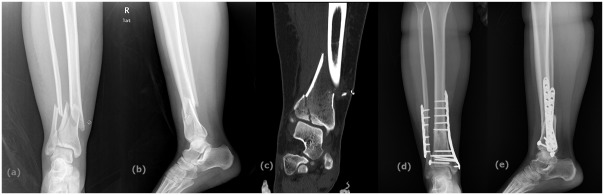

Fig. 1.

A 30-year-old male AO-OTA 43 C1 (a) preoperative X-ray, (b) preoperative computed tomography, (c) early postoperative X-ray, (d, e) postoperative X-ray at 19th month.